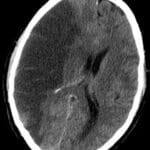

ICH

Admission Template